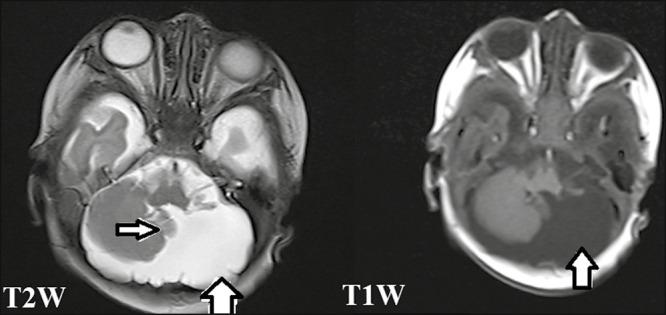

Septo-optic Dysplasia with Cerebellar Hemiagenesis.

A 1-month-old girl child, who was found to have hydrocephalus on prenatal ultrasound, was postnatally evaluated with magnetic resonance imaging (MRI) of brain, which showed two classical findings of septo-optic dysplasia (SOD), namely optic nerve hypoplasia and absent septum pellucidum. In addition, the patient was found to have cerebellar hemiagenesis.